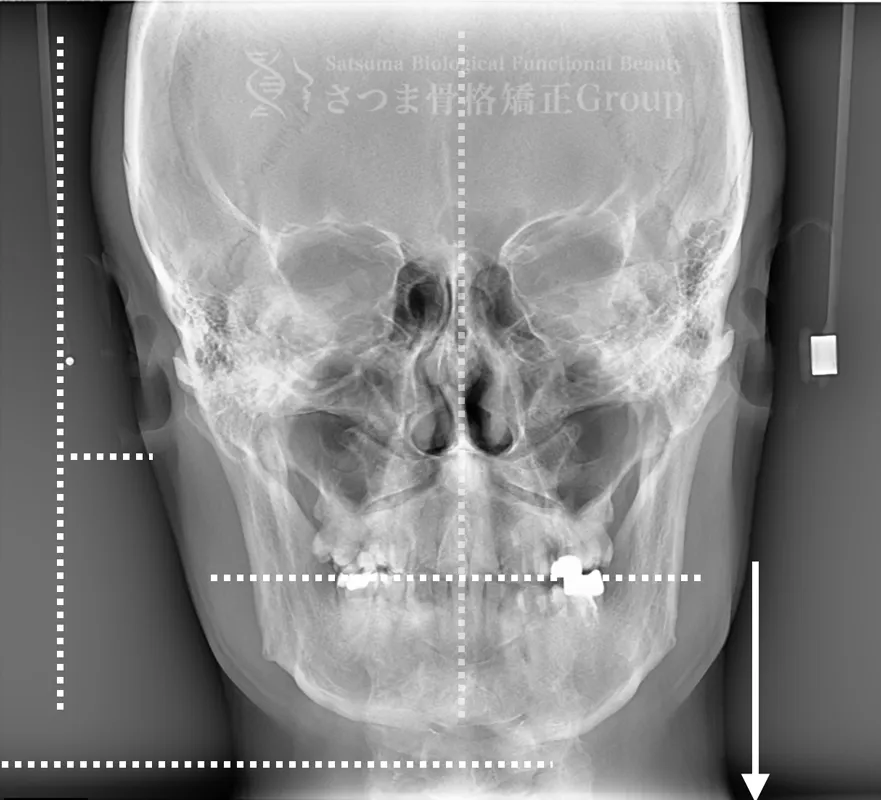

BEFORE

軽度の顎変形症あり

下顎の左方シフト

頚椎の斜頸

中顔面の滑落

Mild jaw deformity present

Leftward shift of the mandible

Cervical spine torticollis

Sagging of the midface

AFTER

下顎の正中誘導

頚椎の斜頸矯正

中顔面の短縮

Midline correction of the mandible

Correction of cervical spine torticollis

Shortening of the midface